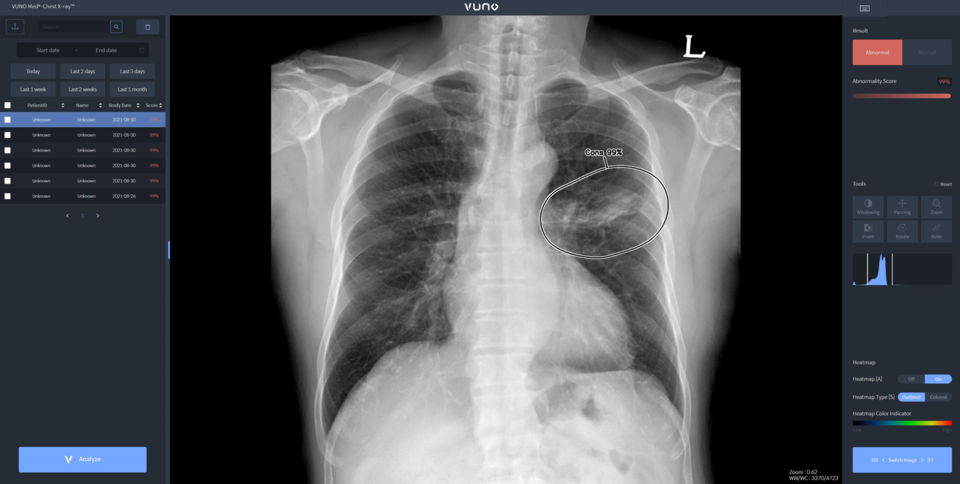

뷰노메드 체스트 엑스레이는 흉부 엑스레이 영상에서 결절, 경화, 간질성 음영, 흉수, 기흉 등 주요 이상소견을 높은 정확도로 탐지하는 AI 솔루션이다. 의료진에게 이상소견의 소견명과 위치를 제시해 결핵, 폐렴 등 주요 폐 질환 진단을 돕는다. 경량화된 모델로 개발돼 다양한 엑스레이 장비에 쉽게 연동할 수 있는 것이 특징이다.